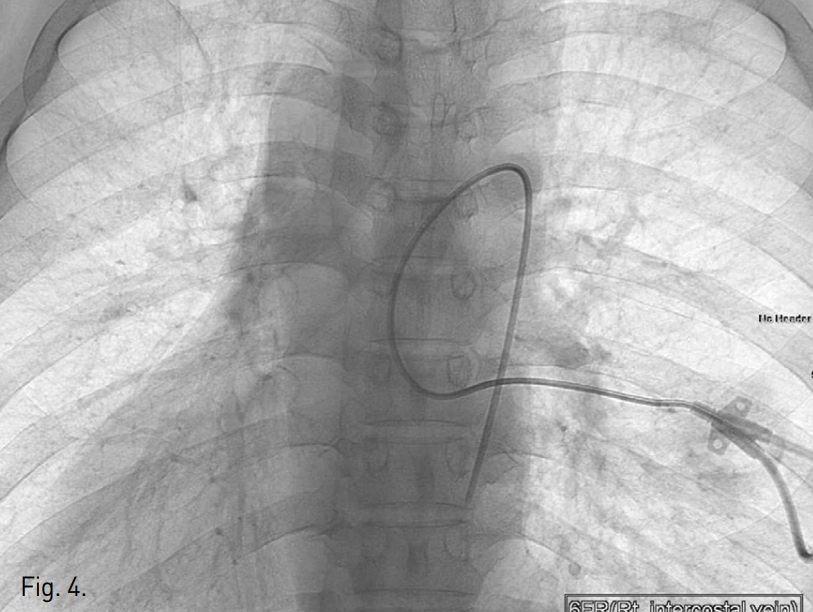

Prone position하에 22G 정맥주사용 바늘로 우측 외흉정맥 천자를 먼저 시도하였으나 조영제의 혈관 외 유출이 발생하여 실패하였음. 초음파 유도하에 우측 7번째 늑간정맥을 micropuncture needle (Cook, Bloomington, USA)로 천자하였고, 투시 유도하에 조영제를 주입하여 늑간정맥을 확인한 다음(Fig. 2) 0.018-inch hairy wire를 삽입하였음. Hairy wire를 거치한 상태에서 5F coaxial dilator를 통해 늑간정맥 조영술을 시행했을 때 기정맥을 통해 심장으로 조영제가 유입되었고(Fig. 3), hairy wire를 우심방까지 전진하였음. 늑간정맥 내로 삽입한 6F peel-away sheath내로 6F dual lumen PICC 카테터 (Vaxel, Navilyst Medical, USA)를 삽입하여 말단부가 우심방 내에 위치하도록 하고 시술을 마쳤음(Fig. 4).

Fig. 4

A radiograph obtained immediately after the procedure demonstrates successful placement of the peripherally inserted central catheter with its tip in the right atrium.